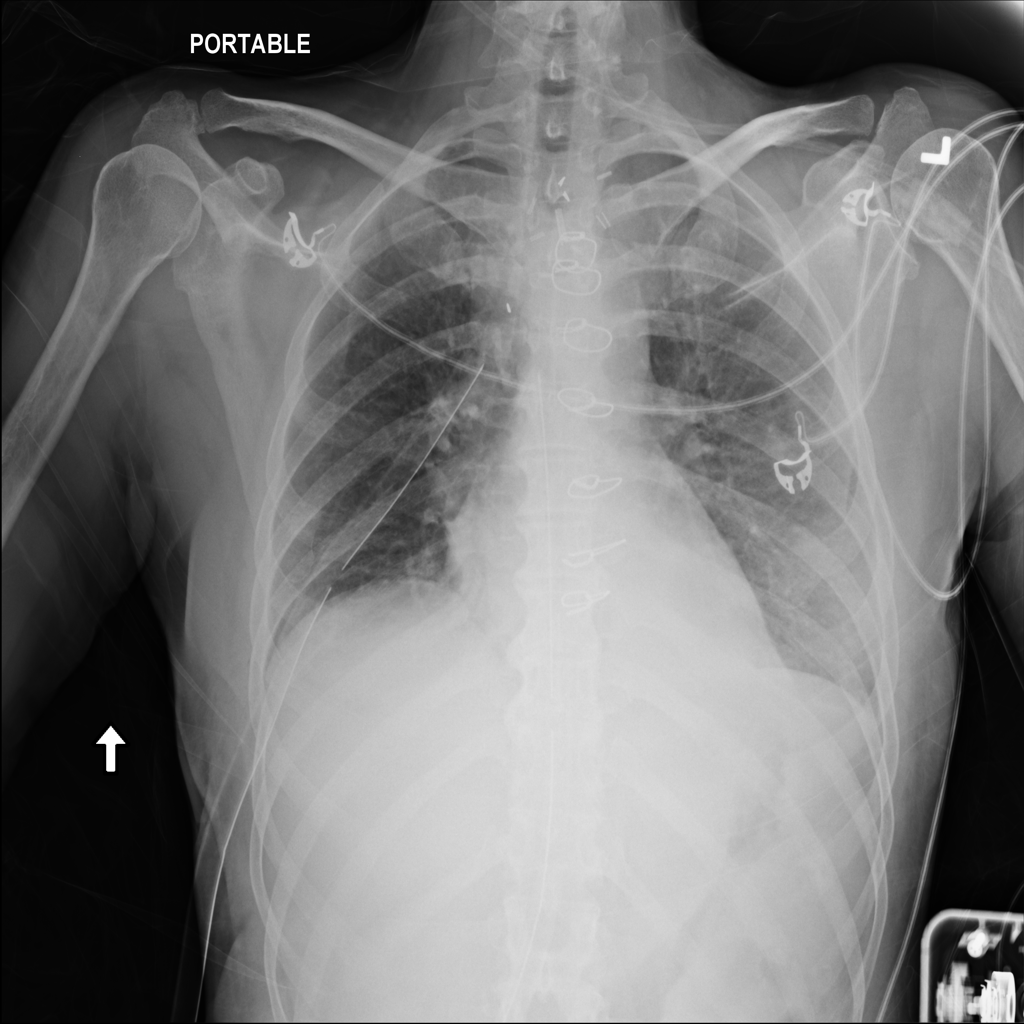

PAT-86C8 · IMG-000Effusion

PAT-86C8 · IMG-000

PA